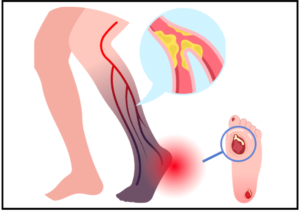

Read MoreVaricose vein Surgery

Varicose veins are a common vascular condition that could be...

Read MoreDiabetic foot surgeon

Diabetic foot surgery refers to surgical procedures performed to treat...